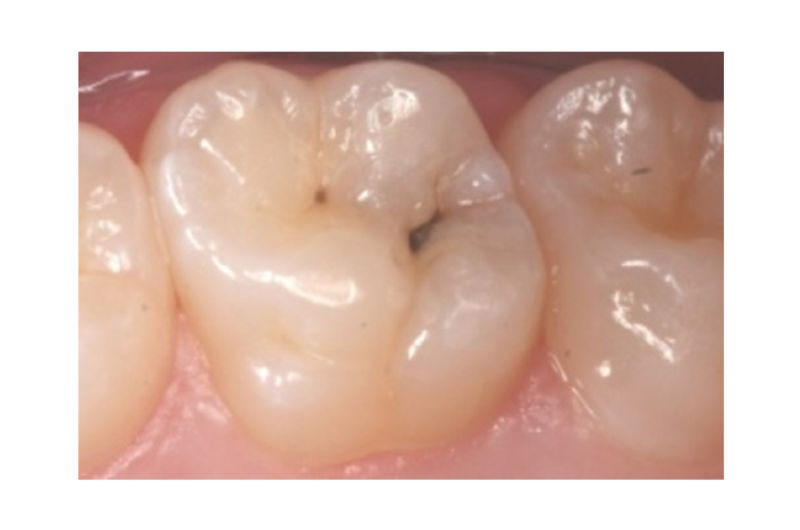

Begyndende hul

Det kaldes et begyndende hul, når ætsningen kun er i emaljen og i det yderste af tandbenet (dentinen).

Begyndende huller behøver man ikke bore ud og lægge fyldning i.

På første billede ses det begyndende hul, som hvid kridtning på tanden.